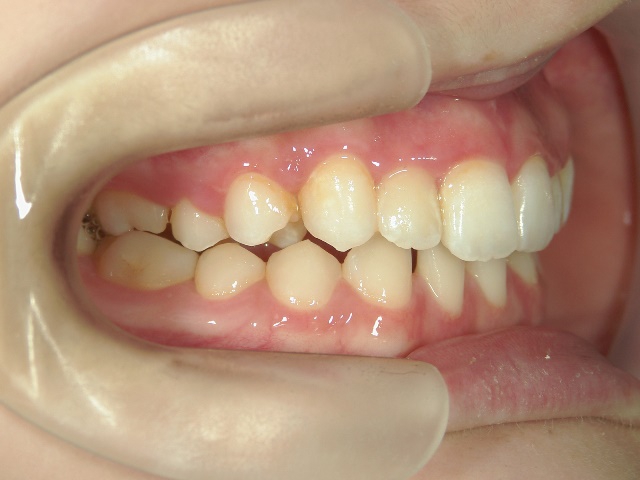

矯正歯科 治療前 正面

矯正歯科 治療後 正面